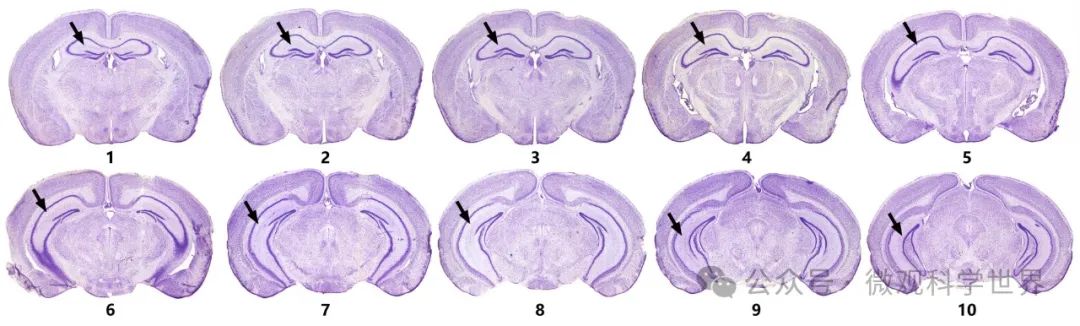

啮齿动物(大鼠、小鼠最常用)是科研实验中研究海马结构的常见选择。为方便与国际通行的脑定位图谱保持一致,目前大多采用冠状面切片。在冠状面切片上,海马由头端到尾端出现多种形态。绝大多数发表文献采用的“标准海马”断面为下图的2、3号代表断面,有时也会用所谓的“大海马”断面,即4 ~ 6号断面。

小鼠脑冠状切面上的海马形态(箭头所示为海马结构)